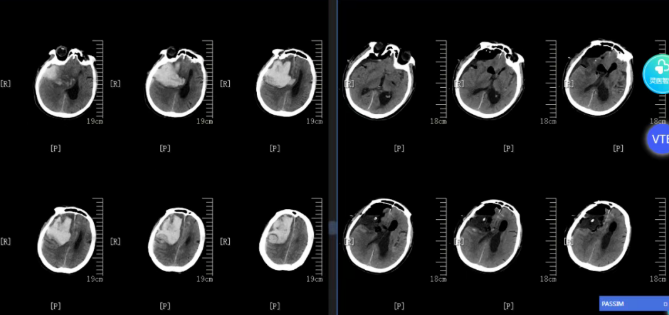

近期收治的两例患者中,一例为14岁青少年,因复发髓母细胞瘤合并出血入院,出血量约30ml;另一例为63岁长者,因突发意识障碍就医,CT提示颞枕叶出血量约70ml,伴有脑疝形成。神经外科团队在完善相关检查后,分别为两位患者开展急诊手术。术后患者意识状态逐步改善,神经功能恢复良好,复查影像学结果达到预期。